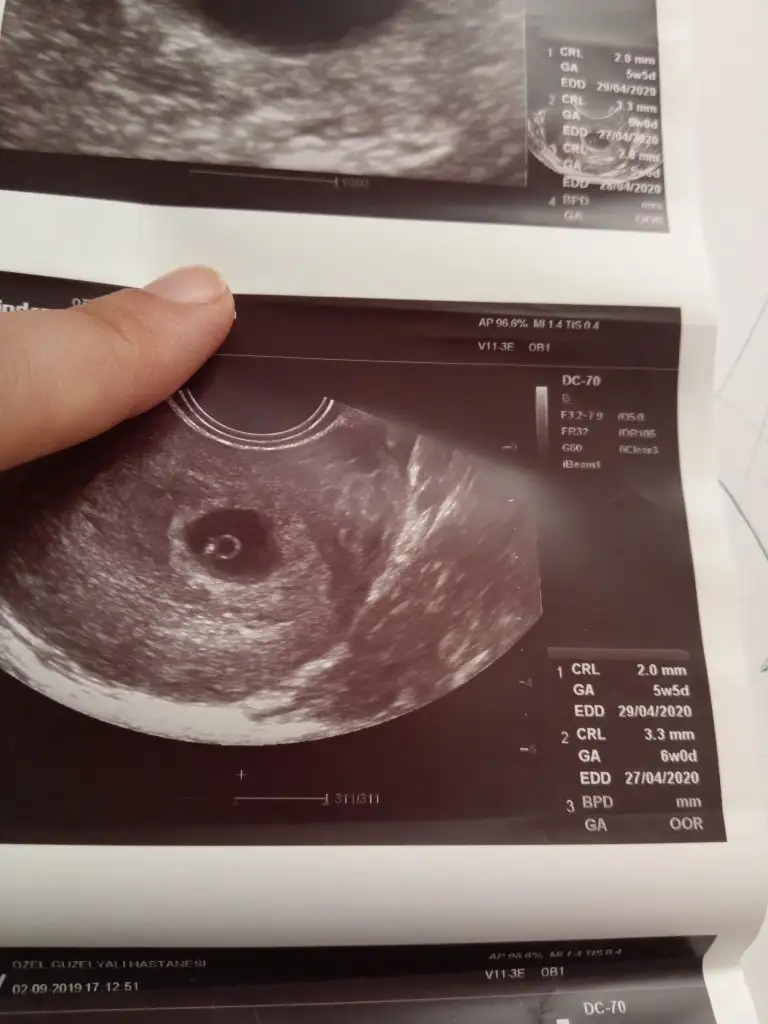

resimde yanlış ölçüm 5+5gunluk yaziyor.

Ama 6+5gunluk burda.yorum yapabilirmisiniz.vajinal ultrason Resim